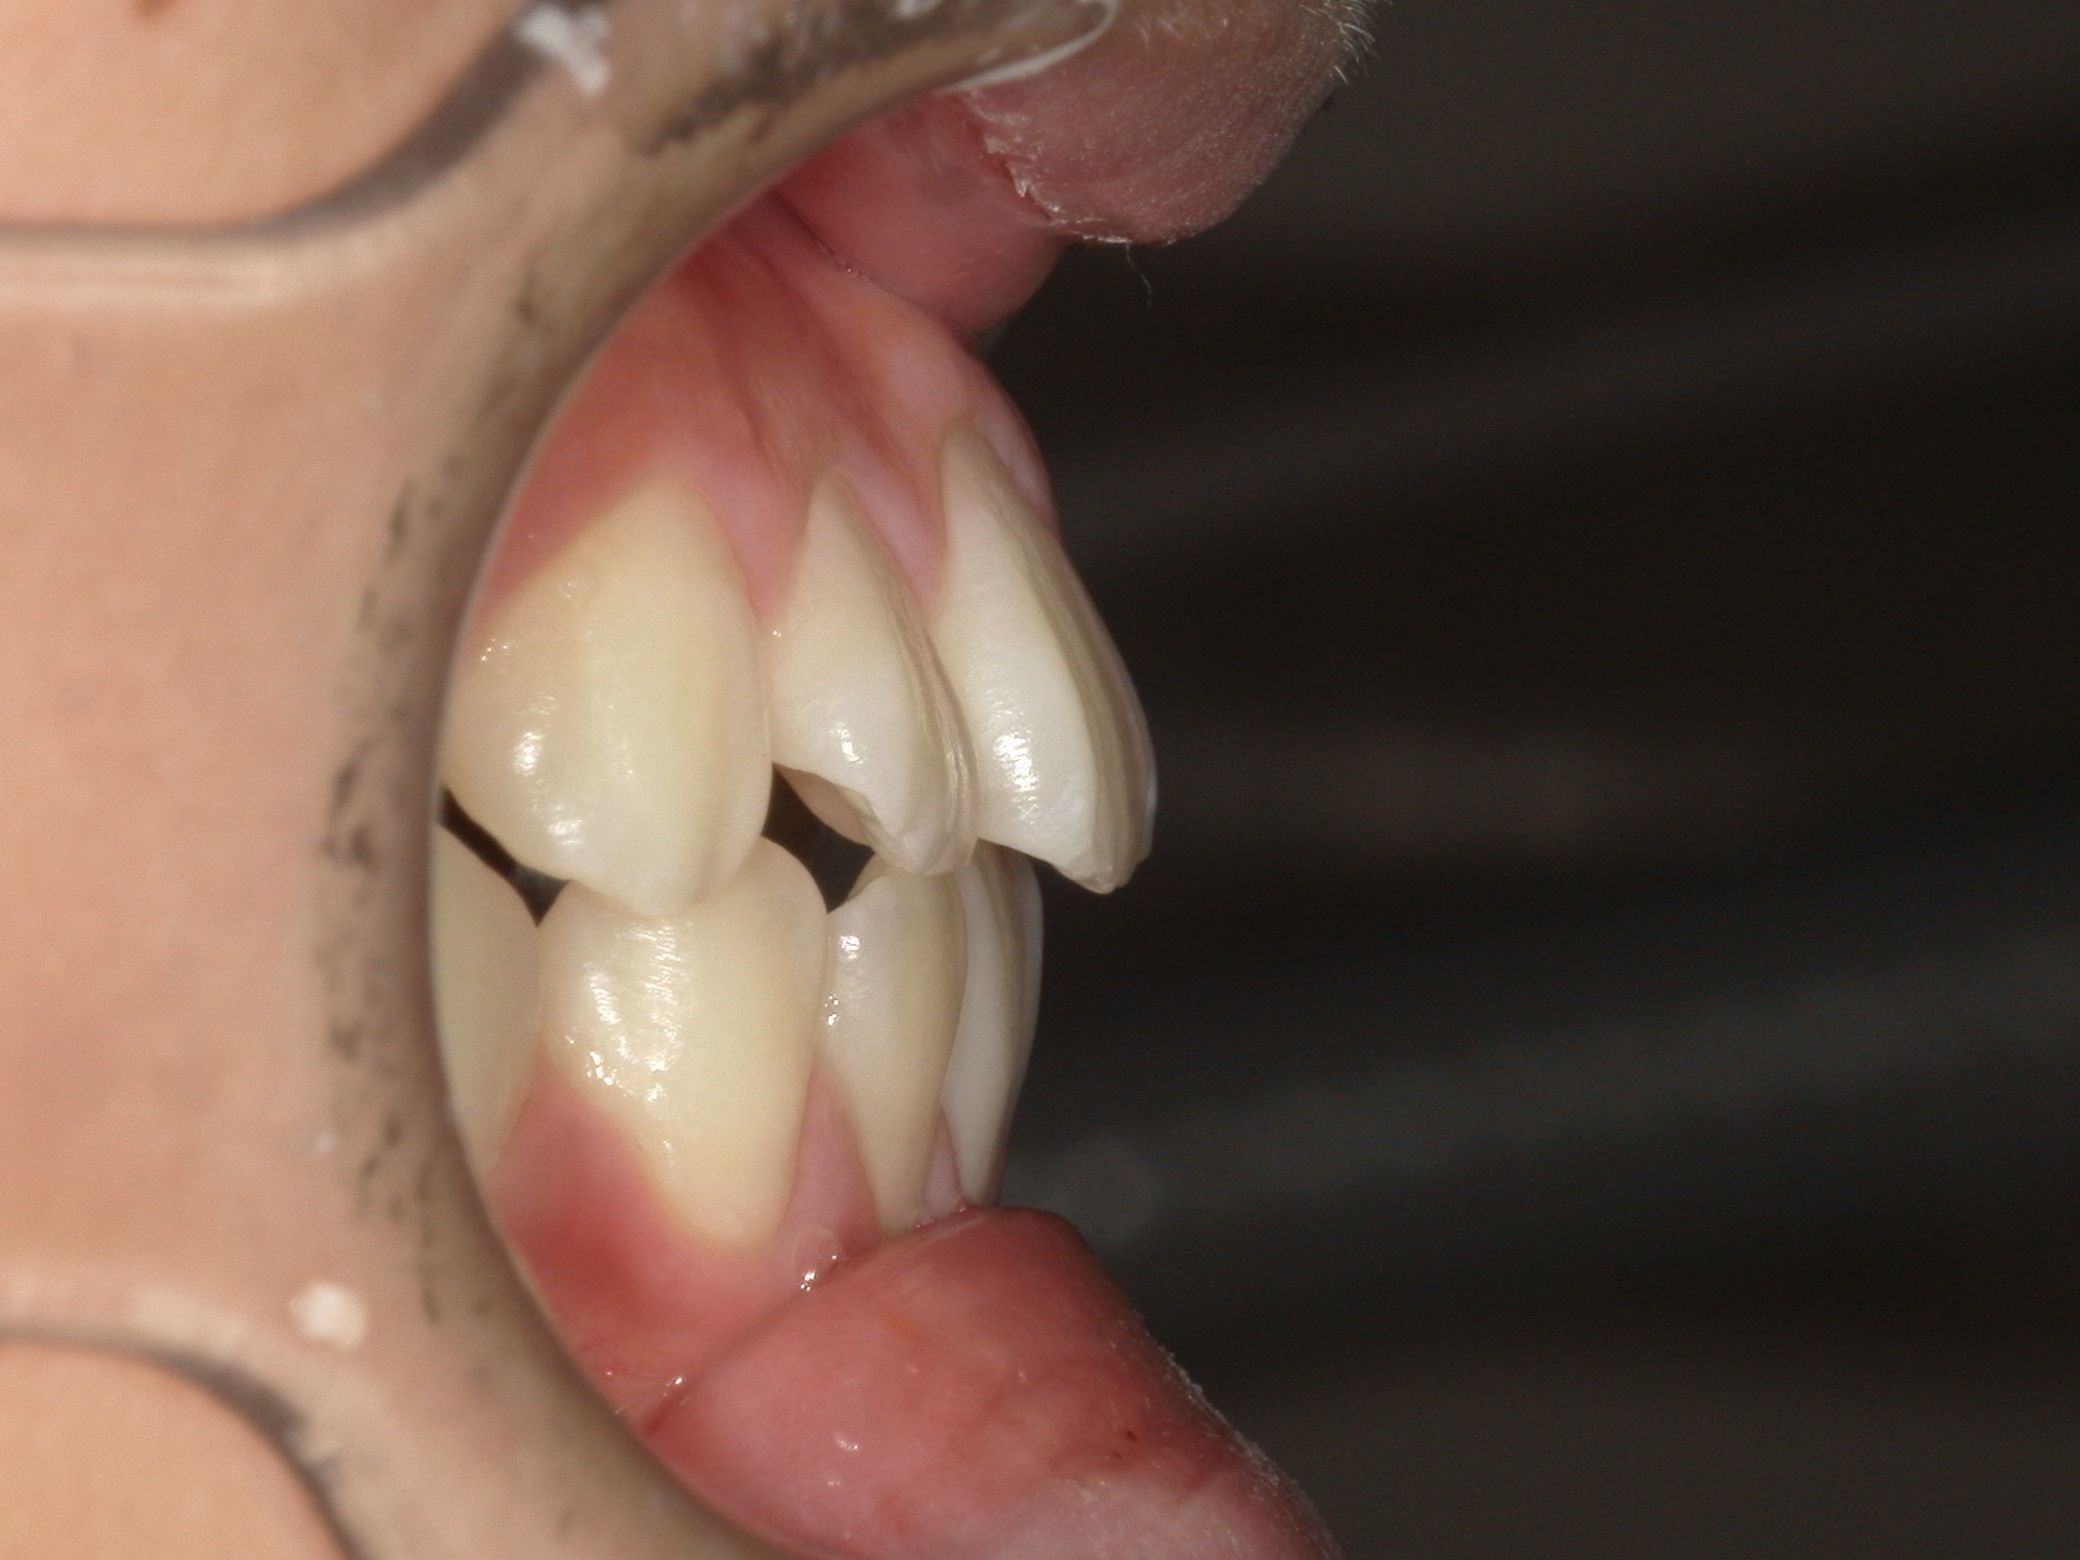

治療後After

ガタつきもなく、きれいなアーチになりました